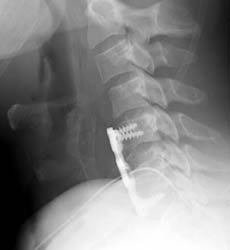

40 year old. male with history of falling off a truck while doing some work had complained of low back pain, muscle spasm, hand and feet numbness, and neck pain since the time of the action. Patient underwent C5-6 and C6-7 anterior cervical discectomy with fusion using anterior plating.

Lateral c-spine -Clik on the image to enlarge Lateral film showing the intact plate and screws for the fusion and nearly imperceptible grafting material in the disc spaces of C5-6 and C6-7.